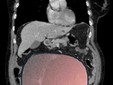

Il caso, definito dai medici un evento “normalmente eccezionale”, è stato preso in carico dalla Chirurgia Ginecologica mininvasiva dell’ospedale Sant’Anna di Torino, diretta dal dottor Paolo Petruzzelli. Nonostante le festività imminenti, la macchina della sanità piemontese si è attivata con una rapidità straordinaria: il 23 dicembre la paziente è stata sottoposta a un intervento durato sei ore che ha visto l’asportazione di una massa di ben 6 chilogrammi e un diametro di 28 centimetri.